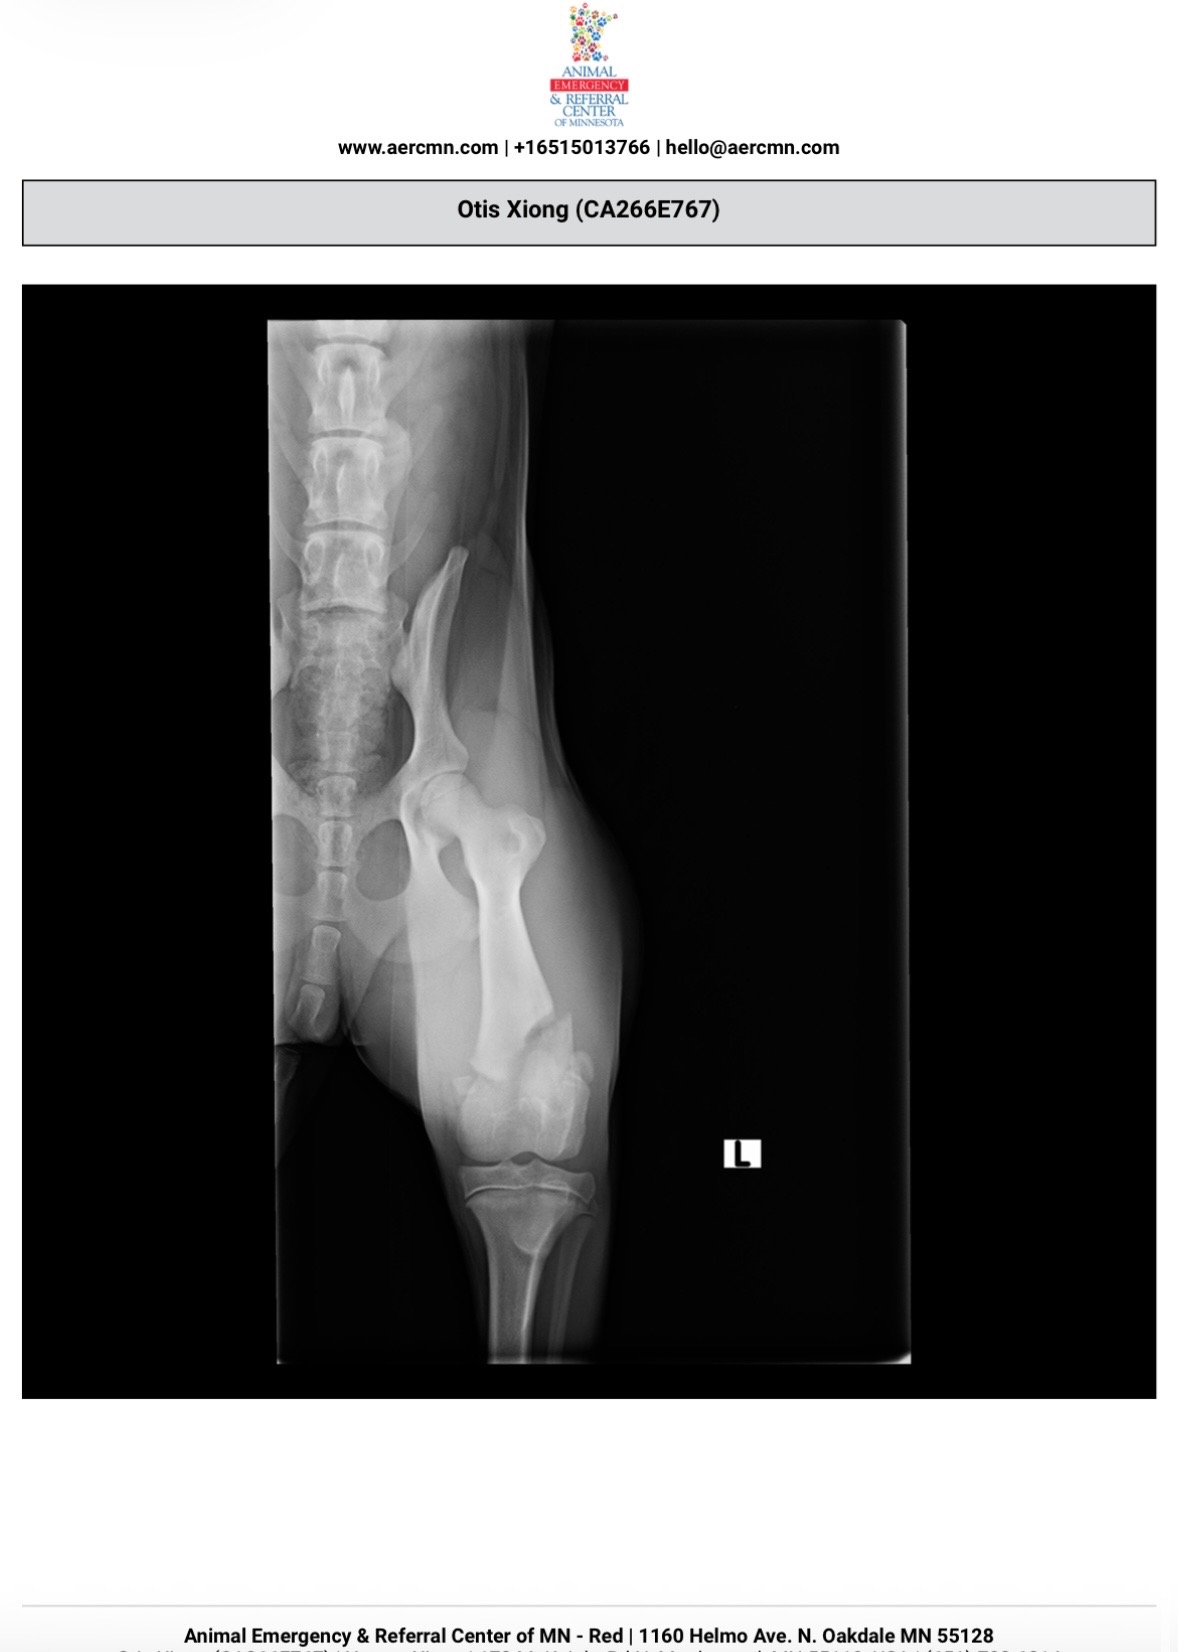

My name is Chiashee. This is really hard for me to share and to ask but our 5 month old puppy Otis recently fractured his left femur after a serious fall. Seeing him not being able to be the same playful, silly and cuddly puppy has been really difficult for my husband and I.

Otis is our baby. If you’ve met Otis, he is loving, chill, and truly a good puppy, we just want him to be okay again. The vet said he needs surgery to heal properly and avoid long term damage. Without surgery, the only other option would be amputation of his left leg.